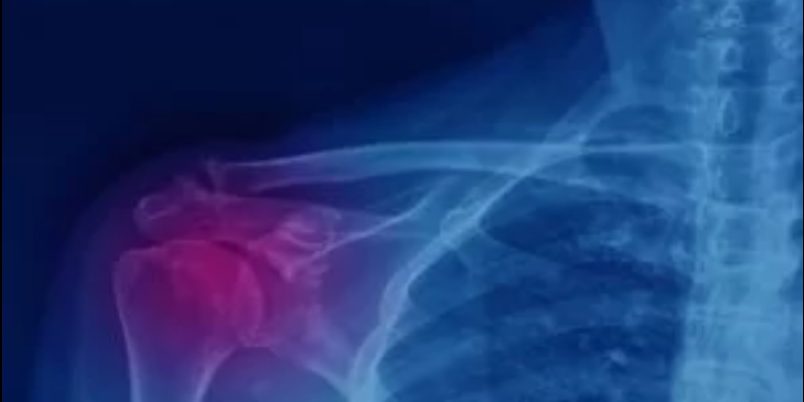

Γενικότερα, το ασβέστωμα στον ώμο αποτελεί μια πάθηση που, εάν εκδηλώσει συμπτώματα, μπορεί να καταστεί αρκετά επίπονη. Η διάγνωσή του γίνεται εύκολα μέσα από τη διενέργεια ακτινογραφίας, όπου εντοπίζεται το ακριβές σημείο της συγκέντρωσης αλάτων ασβεστίου. Η αντιμετώπισή του πραγματοποιείται σε πρώτο στάδιο συντηρητικά, ενώ σε προχωρημένες περιπτώσεις αντιμετωπίζεται από τον ορθοπαιδικό χειρουργό χειρουργικά με τη μέθοδο της αρθροσκόπησης του ώμου.